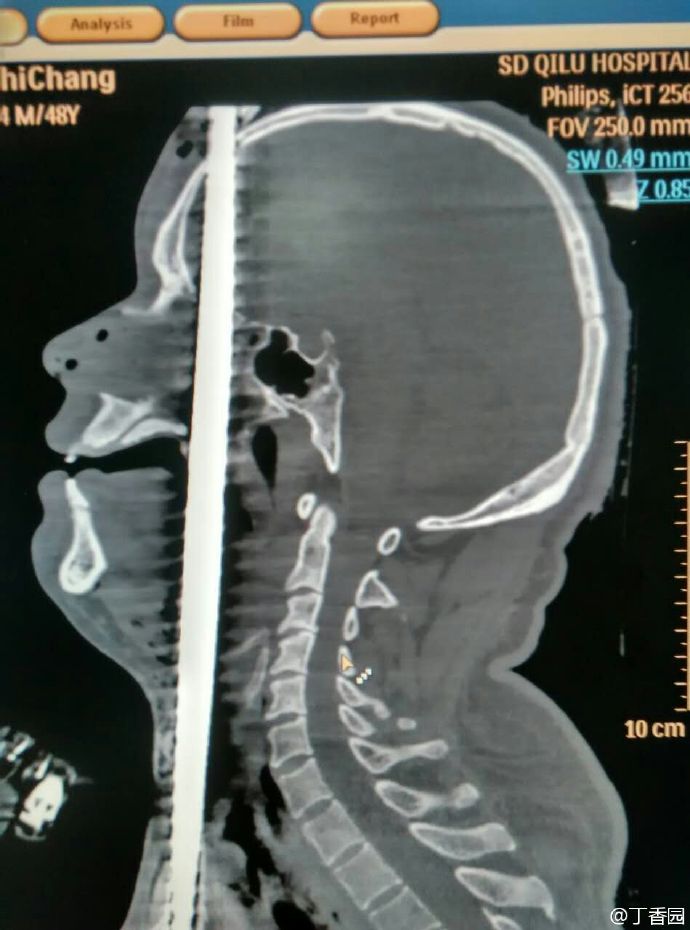

齐鲁医院的病例——正中贯通伤

002.jpg (68.05 KB)

002.jpg

这个不算正中了,只是中间偏表面。[32] 连大脑都没中,才有抢救的可能。不得不说人体很顽强。